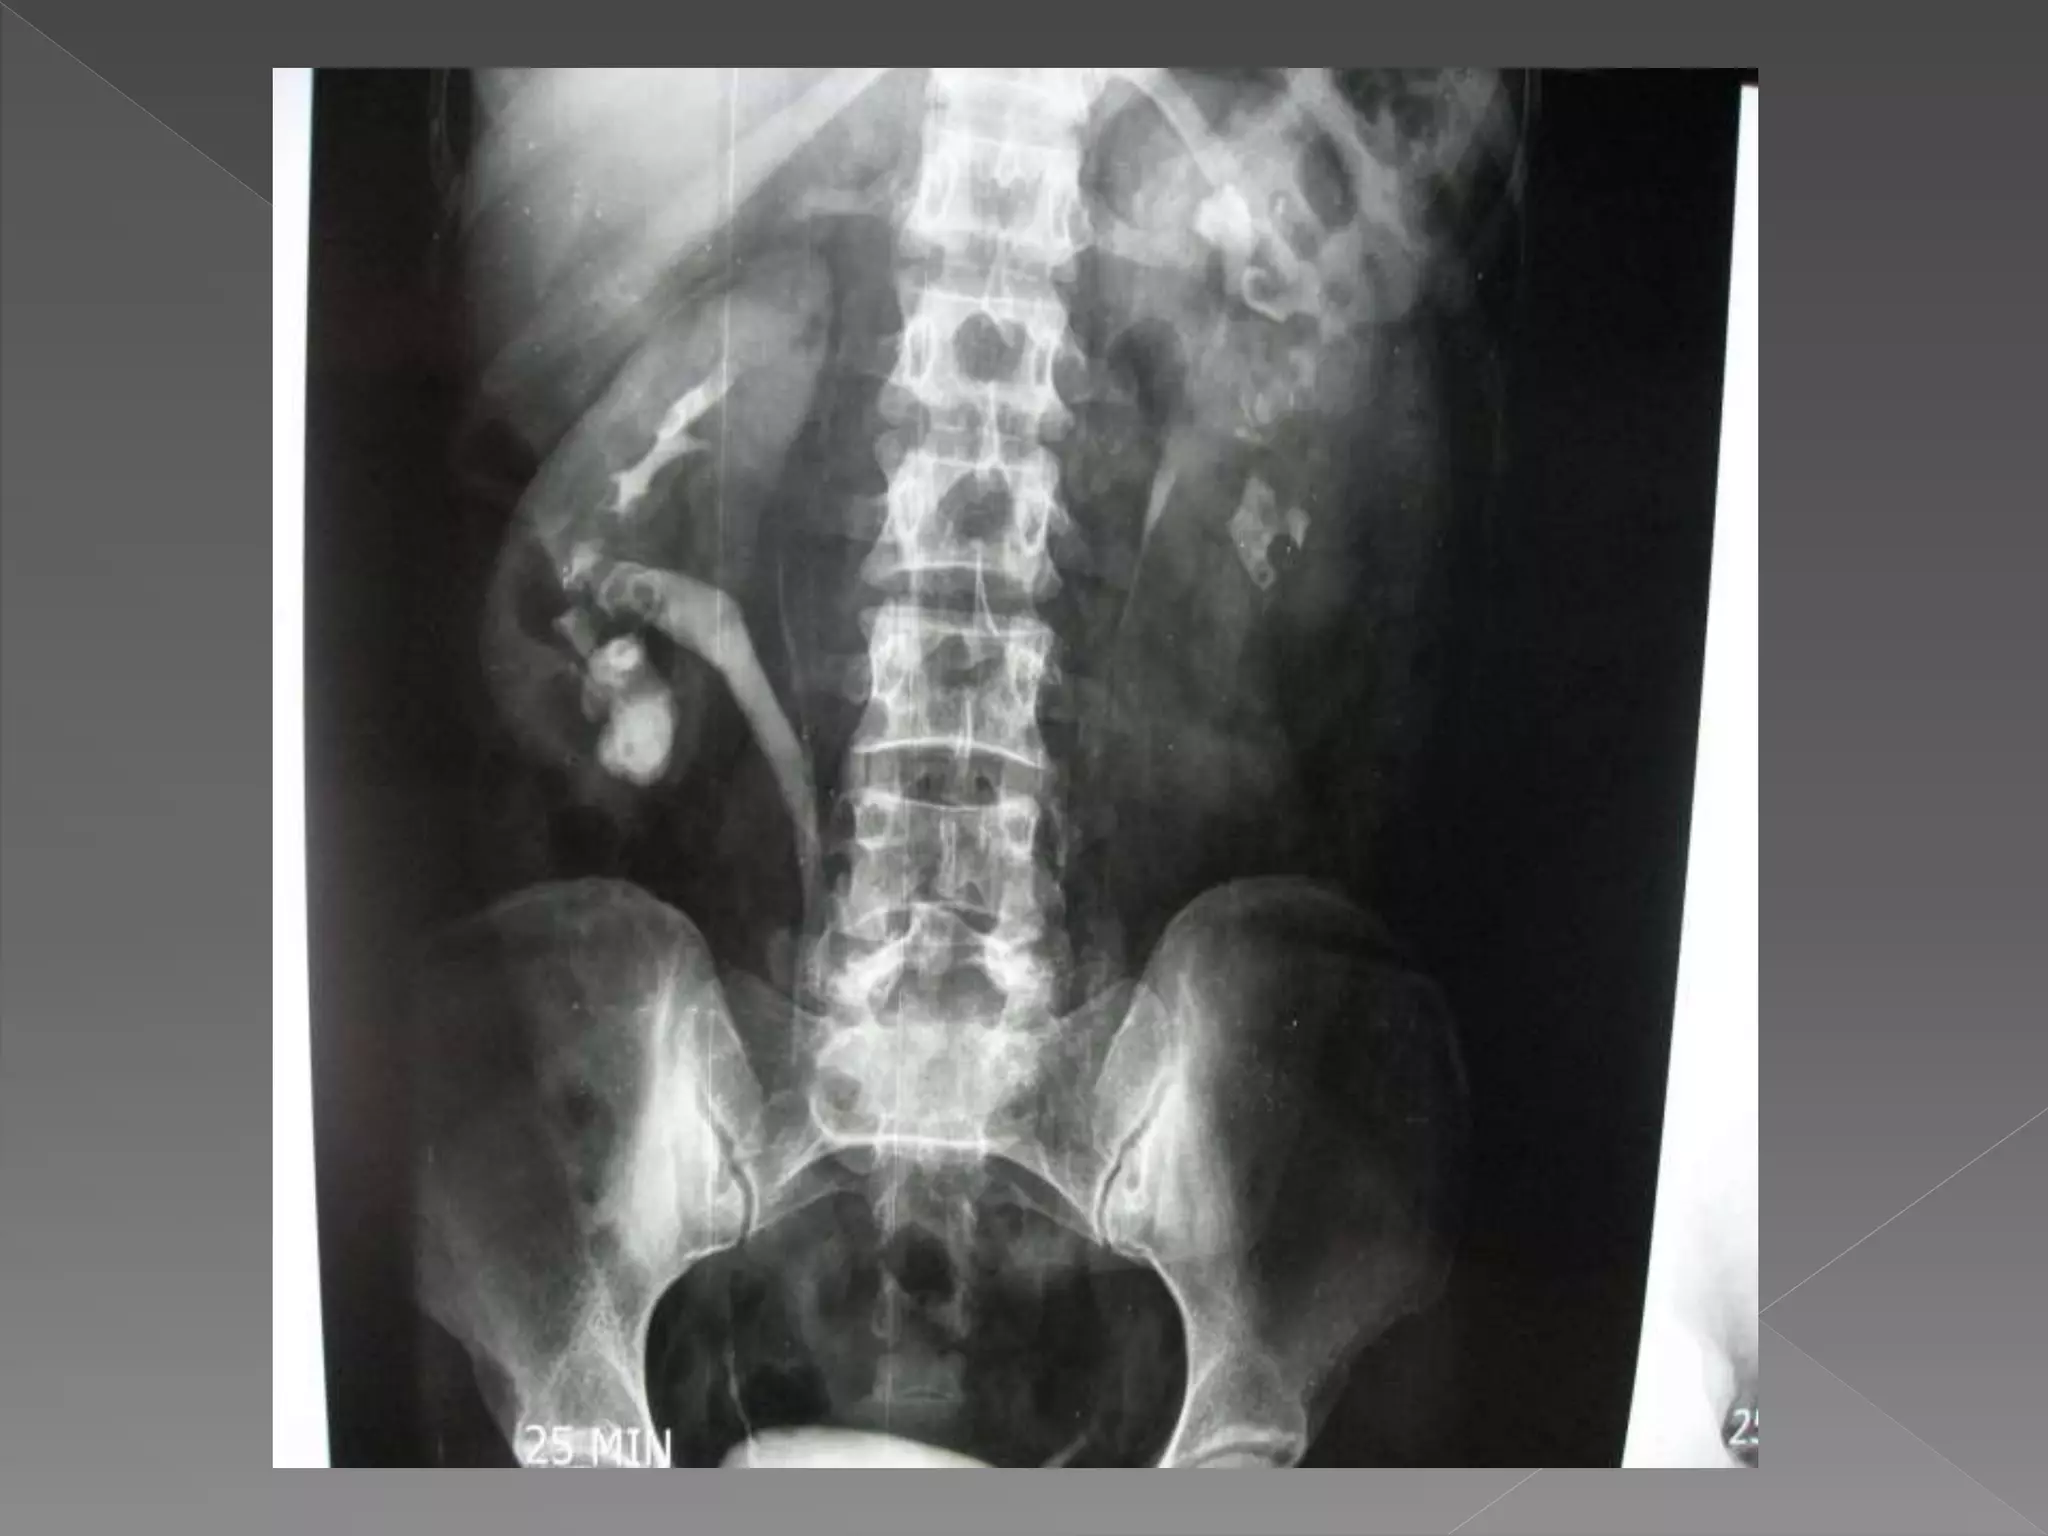

3) 25 mins

X ray films 1)Pre contrast 2) 5 mins 3) 25 mins 4) Post void

 The plainfilm demonstrates calcification within distended upper pole calyces